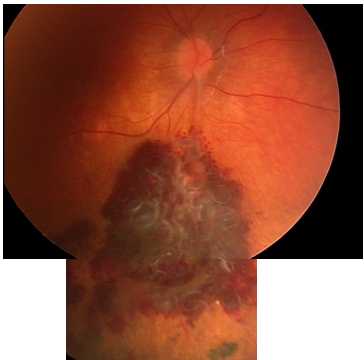

Объективно передний отрезок и стекловидное тело обоих глаз были без изменений, зрачковые реакции сохранены. При биомикроскопии заднего отрезка левого глаза патологических изменений не выявлено. При биомикроскопии заднего отрезка правого глаза: диск зрительного нерва бледно-розового цвета, его границы слегка стушеваны, перипапиллярной и по всему глазному дну множественные полиморфные геморрагии; в макулярной зоне отек с геморрагиями; отмечаются выраженная извитость и расширение сосудов во всех квадрантах; от области диска зрительного нерва в верхней и нижней половинах сетчатки большое количество толстых, сплетенных в «клубок» петель сосудов с артериовенозными анастомозами; по верхне- и нижневисочным аркадам видны облитерированные сосуды; перипапиллярно на 3 часах визуализируется невус хороидеи (рис. 1).

Рис. 1. Фотография глазного дна до лечения: аномальные извитые сосуды с артериовенозными анастомозами, полиморфные геморрагии

Пациентке была проведена антиангиогенная терапия с целью купирования макулярного отека. Для достижения его регресса потребовались 3 интравитреальные инъекции ранибизумаба с интервалом 1-1,5 месяца. Техника проведения инъекций стандартная. На фоне проведенной терапии пациентка отмечала улучшение зрения и исчезновение искажений. Через 5 месяцев от начала лечения максимально корригированная острота зрения правого глаза составила 0,7. Офтальмоскопически: диск зрительного нерва правого глаза бледно-розового цвета с четкими границами; в макулярной области полная резорбция отека; уменьшение количества и размеров ретинальных геморрагий во всех сегментах; четко визуализируются аномальные сосуды: извитые, расширенные, местами полностью облитерированные, с «полосами сопровождения» из фиброзной ткани (рис. 3).

Рис. 3. Фотография глазного дна после лечения: резорбция отека; уменьшение количества геморрагий